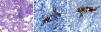

Imagen de microscopia óptica sobre corte histológico de biopsia pulmonar realizada mediante criobiopsia, donde se observa: A)el buen grado de conservación de las estructuras alveolares de la muestra, así como la presencia de infiltrado inflamatorio de predominio linfocitario localizado en el intersticio (hematoxilina-eosina, 40×). B)El estudio inmunohistoquímico muestra la presencia de linfocitosT (marcaje de CD3; 100×) y C)de linfocitosB (marcaje de CD20, 100×). El paciente fue diagnosticado de neumonía intersticial linfocitaria, sin evidencia de linfoma.